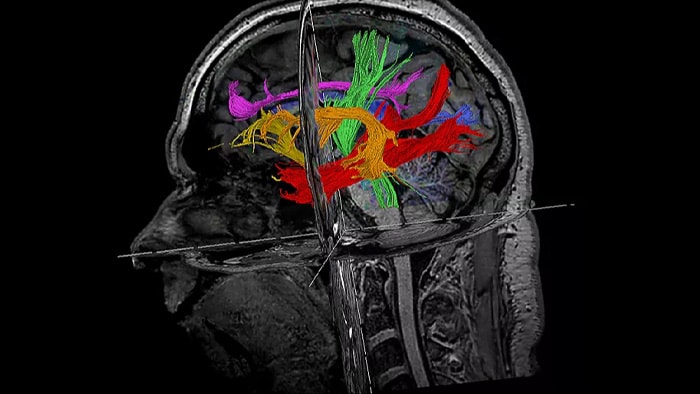

NeuroScience

Co-Creation Facility University Medical Center Utrecht,

The Netherlands